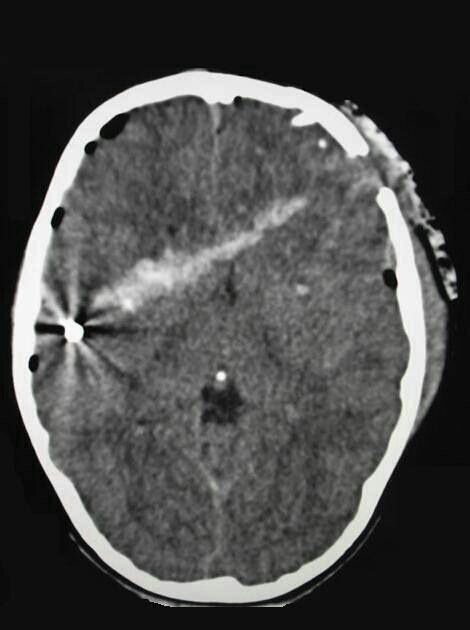

患儿男,7岁。因“间断性腹痛4天,肛门停止排气1天”入院。查体:腹软,左侧腹部局部压痛,无反跳痛,未扪及包块,未见胃肠型及蠕动波。 血生化、肝肾功能及肿瘤指标均在正常范围。腹部CT检查示:降结肠内见突入腔内的软组织块影,直径约3cm。肠镜示:降结肠近脾曲处见突入腔内的肿块影,直径约3cm,考虑为结肠癌。镜下取适量组织行病理检查,结果提示为少量纤维、脂肪组织,其间见少量淋巴细胞浸润。入院后行剖腹探查,术中降结肠脾曲见肿块,直径约4cm,术中诊断为降结肠癌,行根治性左半结肠切除术。病理结果:降结肠弥散性大B细胞淋巴瘤。镜下肿瘤细胞弥散排列、体积较小、较规则、胞质少、核深染、核分裂相偶见,免疫组织化学CD20+,Ki-67增殖指数约90%。 诊断为:淋巴瘤。术后患者行CHOP方案(环磷酰胺+多柔比星+长春新碱+泼尼松)化疗2次,间隔1个月,目前随访9个月无异常。